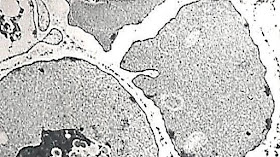

apoyo que nos daba el microscopio electrónico (ME). Este nos mostraba la

realidad de cualquier pregunta sobre morfología microscópica que nos

hiciéramos. Una era evidente y se relacionaba con la hemoglobina S. La veíamos en

el ME como cristales dentro de los eritrocitos (ver la foto) y ya sabíamos que esos eran

los que adoptaban microscópicamente la apariencia de plátano, así se modificaba

su forma y pasaban de ser redondos a lucir bajo la lente del microscopio de

luz, como “camburcitos”.